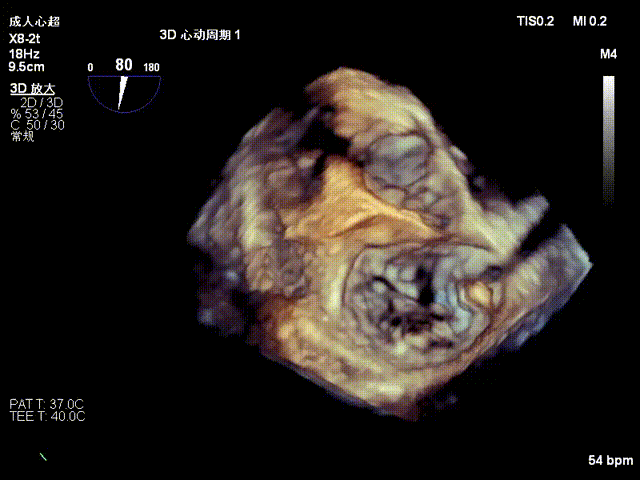

术后二尖瓣反流降至微量,瓣膜夹稳定,功能良好

手术经股静脉-房间隔入路,采用全身麻醉插管,在TEE和DSA引导下完成房间隔穿刺。置入JensClip瓣膜夹系统后,在左房调整瓣膜夹的位置和轴向,后进入左室,在TEE引导下捕捉二尖瓣前后瓣叶,并关闭瓣膜夹。经TEE反复确认手术效果后最终锁定并释放瓣膜夹。由于该病例二尖瓣后叶P2区及部分P3区脱垂,脱垂范围宽度达20mm,术中植入了两枚长宽(LW)的瓣膜夹。术后即刻超声显示瓣膜夹位置稳定,功能良好,二尖瓣反流由术前4+减少至微量,肺静脉逆流和左房压都显著好转,手术圆满成功。术后患者状态良好,目前已安排出院。

结合患者的解剖结构,在保证瓣口不出现狭窄的前提下尽可能地降低二尖瓣反流程度,团队计划植入两枚瓣膜夹。第一枚瓣膜夹尽可能植入于P2P3位置解决大的脱垂,第二枚瓣膜夹植入于P2残余脱垂处。后叶脱垂较高,将会给夹合器的抓捕带来较大难度。术中考虑尝试进行单边分开捕获瓣叶,以降低同时捕获的难度,在捕获瓣叶时,要精准把握时机,在心脏舒张期时,夹合臂才能捕获脱垂的瓣叶,此刻Clip下夹,成功捕获脱垂的瓣叶,尽可能增加瓣叶夹合量,保证瓣膜夹稳定。